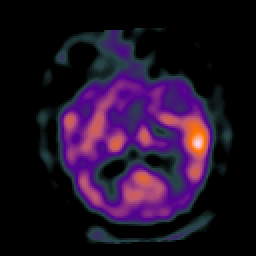

Subacute Stroke, overlay -- Slice #12

[Home][Help][Clinical] Slice 12